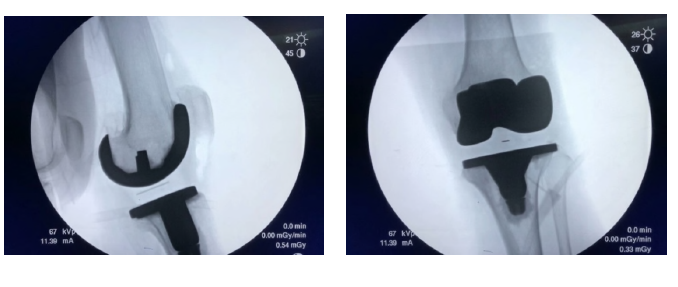

術中精準操作

術后X線片對比